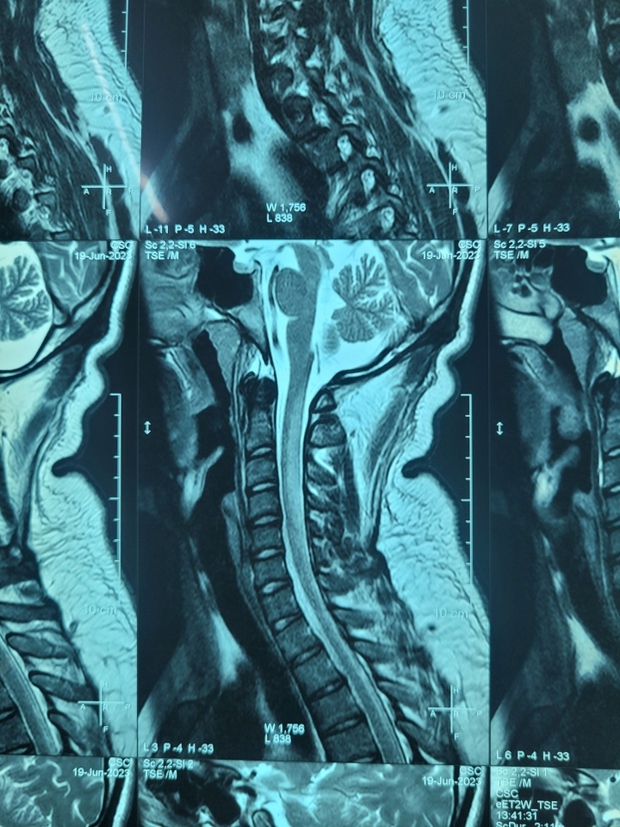

"Việc bệnh nhân xuất hiện các dấu hiệu ngộ độc khí cười nhưng lại không đến cơ sở y tế gần nhất để thăm khám mà tự ý mua thuốc điều trị ở nhà sẽ làm tăng các triệu chứng, tổn thương nặng khi nhập viện, để lại hậu quả nghiêm trọng, ảnh hưởng đến sức khỏe về lâu dài. Hiện, bệnh nhân tổn thương tủy cổ đoạn dài từ C1 đến C6, liệt không đi lại được", BS Hà cho hay.

Hình ảnh MRI cột sống cổ, bệnh nhân tổn thương tủy cổ từ C1-C6